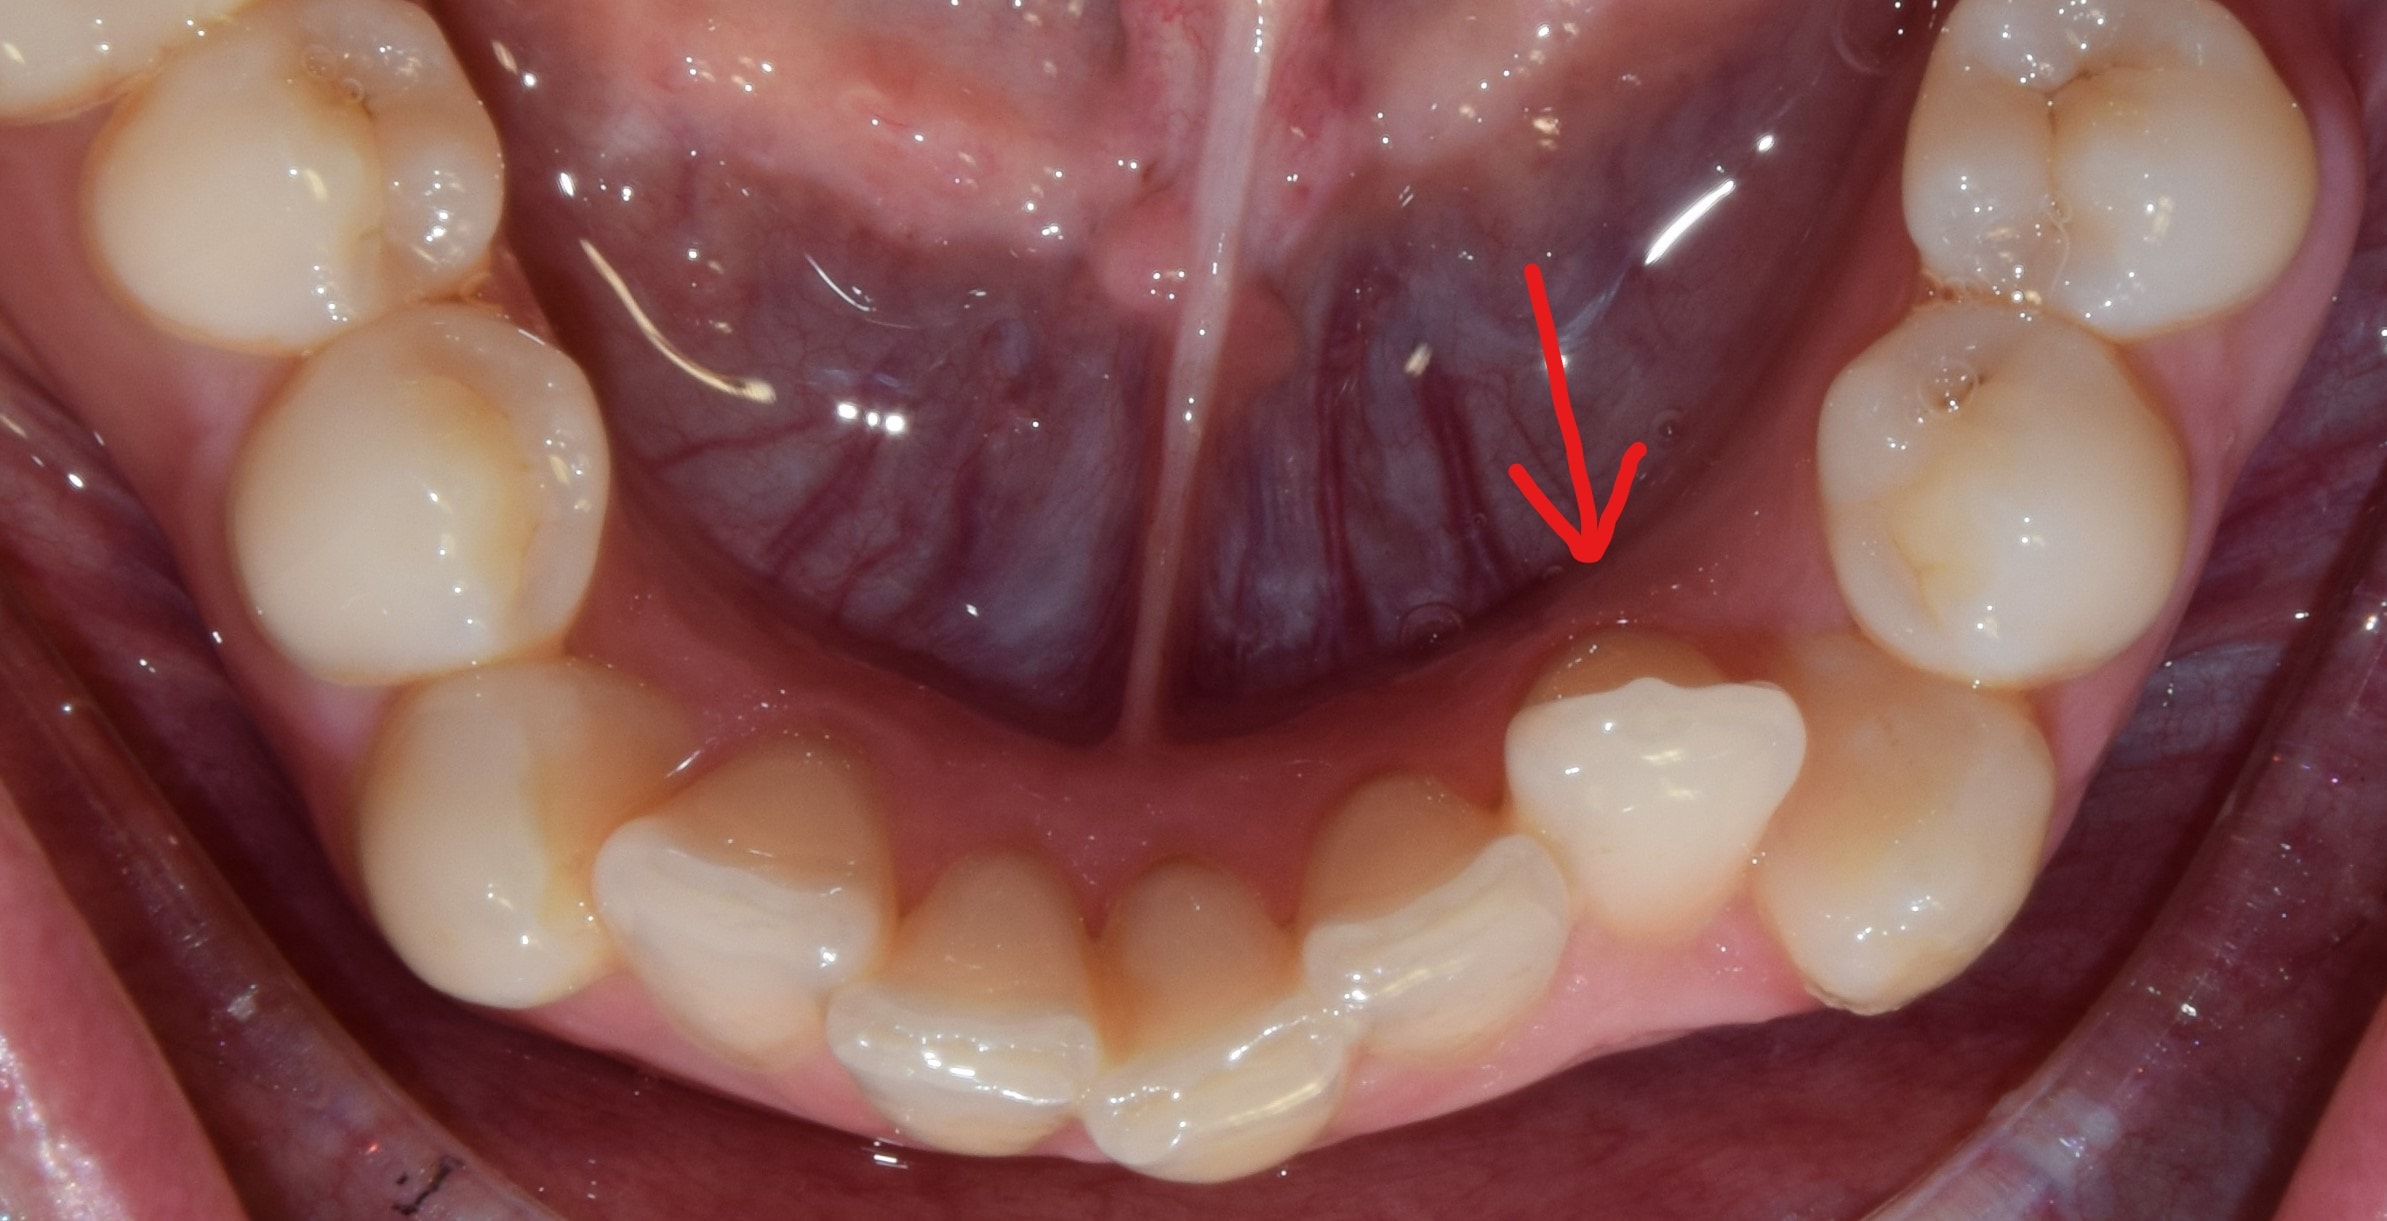

Ajakfék

Az ajakfék nem más, mint az ajkak mozgását szabályozó, korlátozó nyálkahártya tömörülés, mely az alsó és felső első metszők fölött-között helyezkedik el. A túlságosan kifejezett ajakfék beszédproblémát, ínyvisszahúzódást, vagy akár rést is okozhat a metszőfogak között. A köteges, kifejezett ajakféket egy kis szájsebészeti beavatkozás során korrigálni lehet, legkíméletesebben lézerrel.

Diasthema medianum

Gyakori fogszabályozási probléma a két felső nagymetsző között jelentkező rés. Ellátását számos faktor befolyásolja. A vegyesfogazatban gyakori, legtöbbször normális jelenség, ami később spontán záródhat, ezért túlságosan korai ellátását semmi sem indokolja. Diasthemat eredményezhet például kifejezett ajakfék, számfeletti fog, kismetsző csírahiány.